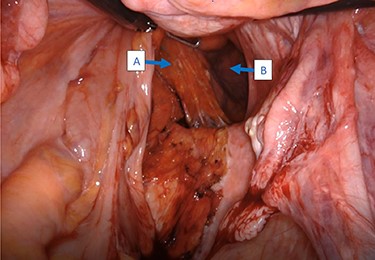

Intraoperatively, cystoscopy and intraurethral ICG injection were performed as a routine practice to aid with the identification and protection of ureters in redo pelvic surgeries. The abdomen was accessed using the Veress needle technique, and robotic trocars were placed in transverse fashion at the level of the umbilicus. Initially, a medial-to-lateral mobilization of the descending colon was performed. The mesorectal fascial plan was entered posteriorly and the rectum was circumferentially mobilized. The pelvic defect was encountered on the right side, and it was noted that the rectum was redundant, folded on itself and contained by the hernia sac (Fig. 2). Using meticulous dissection, it was reduced completely. The hernia roof consisted of the gluteal skin only. The hernia neck was wide and consisted of defects in the levator muscle. The anal canal formed part of the hernia wall.

Intraoperative view of the rectum (A) herniating through a defect in the pelvic wall (B).